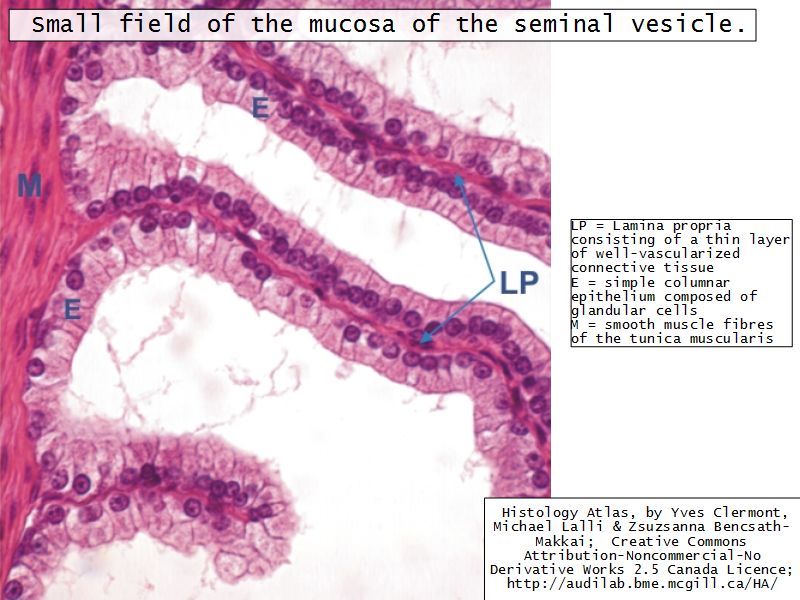

Vesicula seminalis

Slide 81Vesicula seminalis

- Mucosa

- Epithelium

- Lamina propria

- Muscle layer

Mucosa

- Lumen

- Irregular

- Store secretions

- Pseudostratified columnar epithelium

- Lamina propria

- Contains AVL

- Folded mucosa ^^ surface area

Muscle layer

- Inner circular

- Outer longitudinal